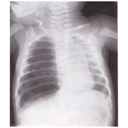

pneumothorax.jpg